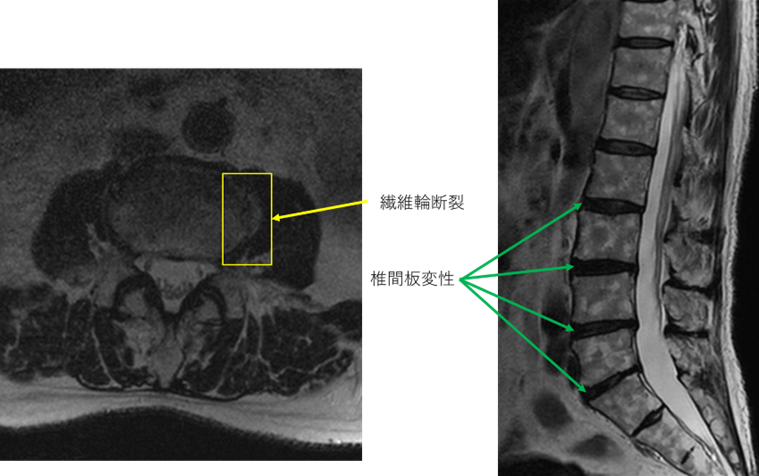

画像及び所見について

L1/2: 異常なし

L2/3: 椎間板変性症

L3/4: 椎間板変性症、繊維輪断裂

L4/5: 椎間板変性

L5/S: 椎間板変性

以上の事が画像上認められます。

2/3,3/4,4/5,5/s に

椎間板変性、線維輪断裂 を認め、主症状の原因の可能性が高い。